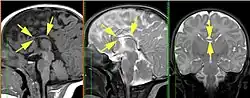

Агенези́я мозо́листого те́ла (АМТ) — редкий врожденный дефект (врожденное заболевание), при котором наблюдается полное или частичное отсутствие мозолистого тела. АМТ может быть обнаружена изолированно на МРТ, но чаще сочетается с множественными пороками развития[1].

Диагностика нарушения осуществляется внутриутробно, либо после рождения с помощью УЗИ, МРТ, либо КТ.

Основные диагностические критерии, позволяющие заподозрить наличие АМТ:

- радиальный паттерн борозд медиальной поверхности мозга — борозды медиальной поверхности гемисфер мозга отходят от крыши III желудочка, поясная извилина не сформирована;

- параллельность тел боковых желудочков головного мозга

- расстояние между телами боковых желудочков увеличено

- аномальное расширение задних рогов боковых желудочков

- отсутствие прозрачной перегородки

- высокое расположение III желудочка.